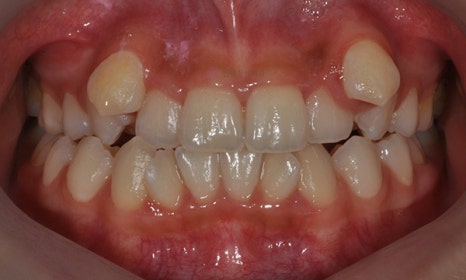

본 환자분은 오른쪽 아래 유구치(유치 어금니)가 남아있고 그 안쪽에 두번째 작은 어금니가 나와 있었습니다. 나머지 세 부위의 두번째 작은 어금니들은 영구치 치배가 없어 유치 어금니로 사용해온 상태였습니다. 왼쪽 아래는 뿌리만 남아있었고, 오른쪽 위에는 유치 어금니가 빠지고 공간이 비어 있었으며, 다행히 왼쪽 위 유치 어금니는 아직 남아 있는 상태였습니다. 아래는 오른쪽의 유치 어금니 및 왼쪽의 비어 있는 어금니 공간이 많이 남아 있고, 상대적으로 위에는 어금니 공간이 부족하여 위아래 앞니도 제대로 물리지 않고 있었습니다.

오른쪽 아래 치아들과 같이 치아가 겹쳐져 있게 되면, 교합이 맞지 않을 뿐만 아니라 그 사이 부위의 구강위생관리가 제대로 이루어질 수 없기 때문에 충치가 생길 확률이 높으며, 잇몸도 안좋아질 수 있습니다.